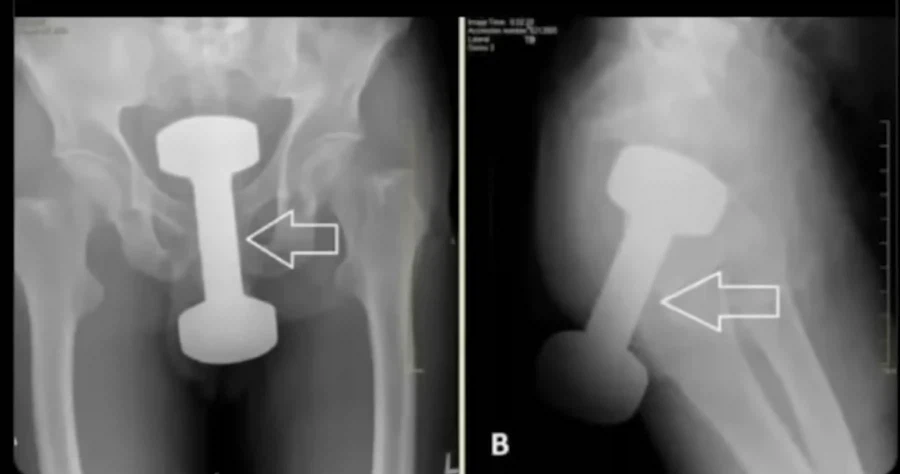

[유머] 헬스장에서 덤벨을 깔고 앉지마라는 이유. [19]

저게 어케 저렇게 들어가지...

알몸으로 앉아있다 쑥 들어갔다..? 아니 저정도가 쑥 들어가는 수준인가?

저건 아무리 개발했다해도 강제로 집어넣은거 아냐?.. 골반을 출산급으로 벌려야하는거 아닌가

와... 보는순간 내가 다 움찔했네... 저게 들어가냐.... 남자같은데 저게 저렇게 문제없이 들어갈수 있는건가?... 뼈 문제 안생기나?...